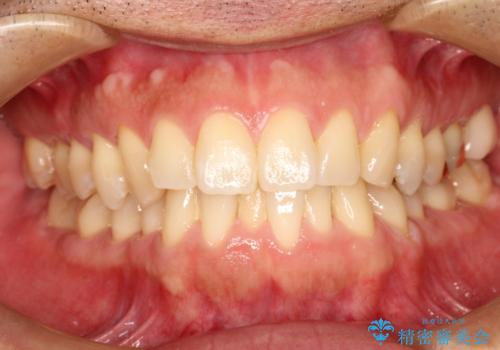

ワイヤーによる全体的ながたつきの矯正治療